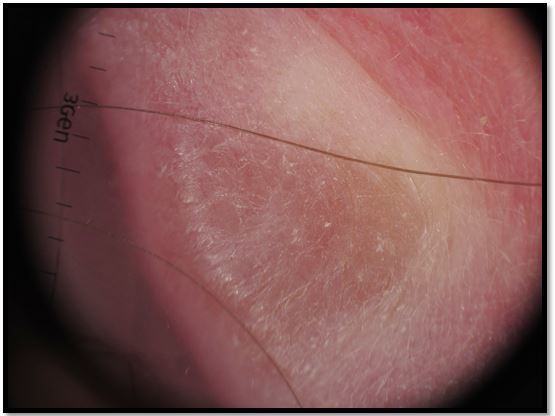

Figure 2. Dermoscopy of right helical rim shows yellow to orange globular-like area that suggests a granulomatous process such as cutaneous sarcoidosis.(6,7)

A 58-year-old Caucasian woman, a non-smoker, presented with an asymptomatic pink telangiectatic nodule with 2 adjacent smaller papules on her right helical rim (Figure 1, please click to enlarge). The lesion had grown over the past decade. A skin biopsy was obtained to rule out basal cell carcinoma.